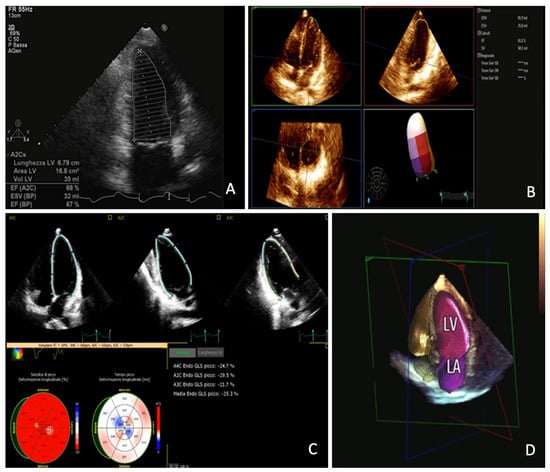

A representative case is shown in Figure 6.

Figure 6.

Panel (A): bi-dimensional echocardiography measurement of left ventricle ejection fraction; Panel (B): three-dimensional echocardiography measurement of left ventricle ejection fraction; Panel (C): Left Ventricle global longitudinal strain assessment; Panel (D): three-dimensional left ventricle and left atrium automatic measurement with artificial intelligence algorithm.